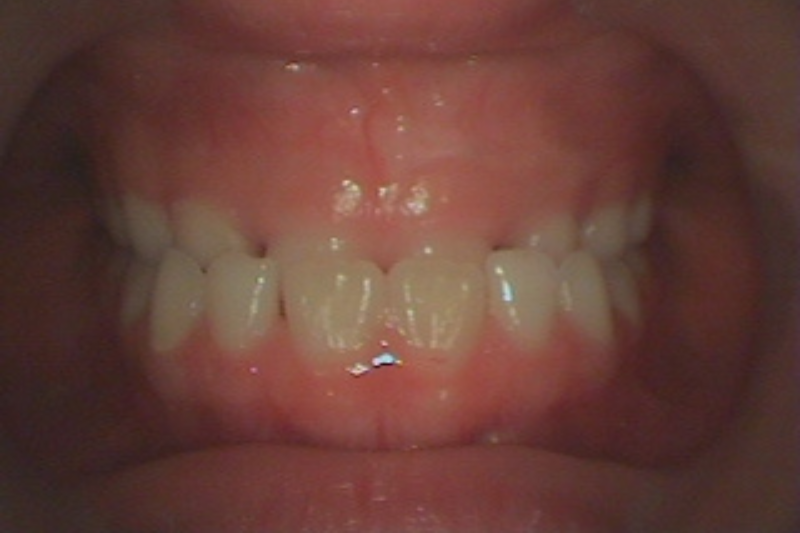

Before

症例2 治療前

After

症例2 治療後

年齢・性別 12歳・女の子

治療内容 マイオブレイス

治療期間 3年10ヶ月

費用 400,000円(税込)

主なリスク 矯正装置の装着時に違和感や痛みが生じる場合があります。

装置の使用状況により治療期間が延長する場合があります。

治療後、保定装置を使用しない場合は後戻りする可能性があります。

治療結果には個人差があります。